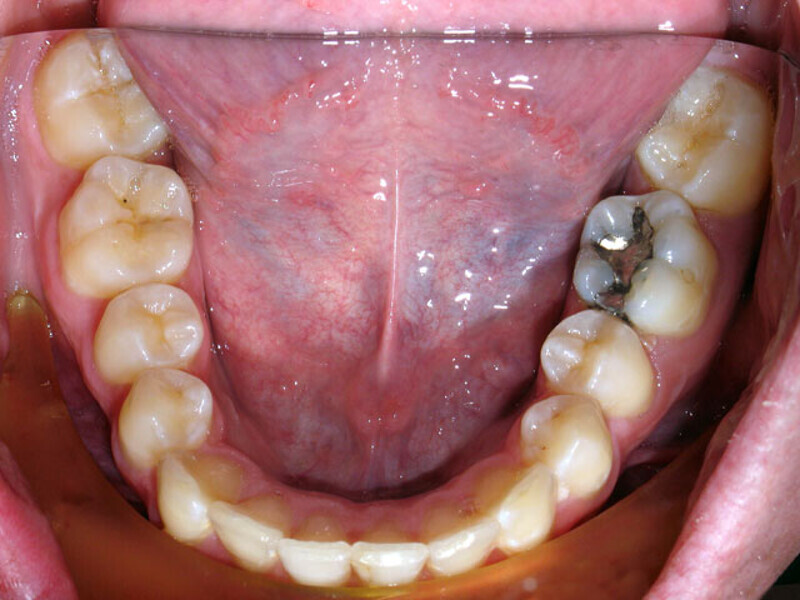

ClearCorrect treatment of crowding